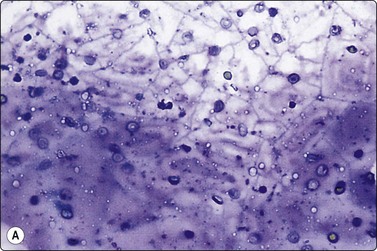

Fig. 6.12 Florid lymphocytic pattern of HT, 2 cases

(A) Polymorphous population of lymphoid cells with high lymphoid : epithelial cell ratio (follicular cells in top center, MGG, IP); (B) Cellular smears, mainly reactive lymphoid cells, cluster of follicular cells in centre (MGG, HP).

The ‘lymphocytic’ pattern of HT occurs in children and young adults with a shorter history of the disease and absent or low antibody titers.88 Smears are dominated by a mixed population of lymphoid cells including centroblasts, immunoblasts and dendritic reticulum cells from germinal centers characteristic of a reactive lymphoid proliferation (Fig. 6.12). Germinal center histiocytes have plentiful pale cytoplasm and oval or indented histiocytoid nuclei with granular chromatin. They are often clustered and associated with lymphoid cells, some of which lie within their cytoplasm. Histiocyte-lymphocyte rosettes or lympho-histiocytic clusters may be seen. Lymphoid : follicular cell ratios are often as high as 10 : 1 with epithelial cells so inconspicuous that smears resemble reactive lymphoid hyperplasia (Fig 6.12 A).